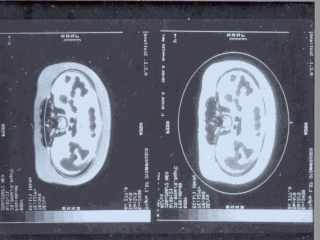

In the literature there is much attention on fat distribution and its relationship to insulin resistance. These pictures show the peritoneal fat grains directly into the portal circulation and metabolically much more active than subcutaneous adipose tissue. So, the constant exposure of the liver to free fatty acids being released in large amounts from this fat may explain the insulin resistance and hyperinsulinaemia of the centrally obese subjects.